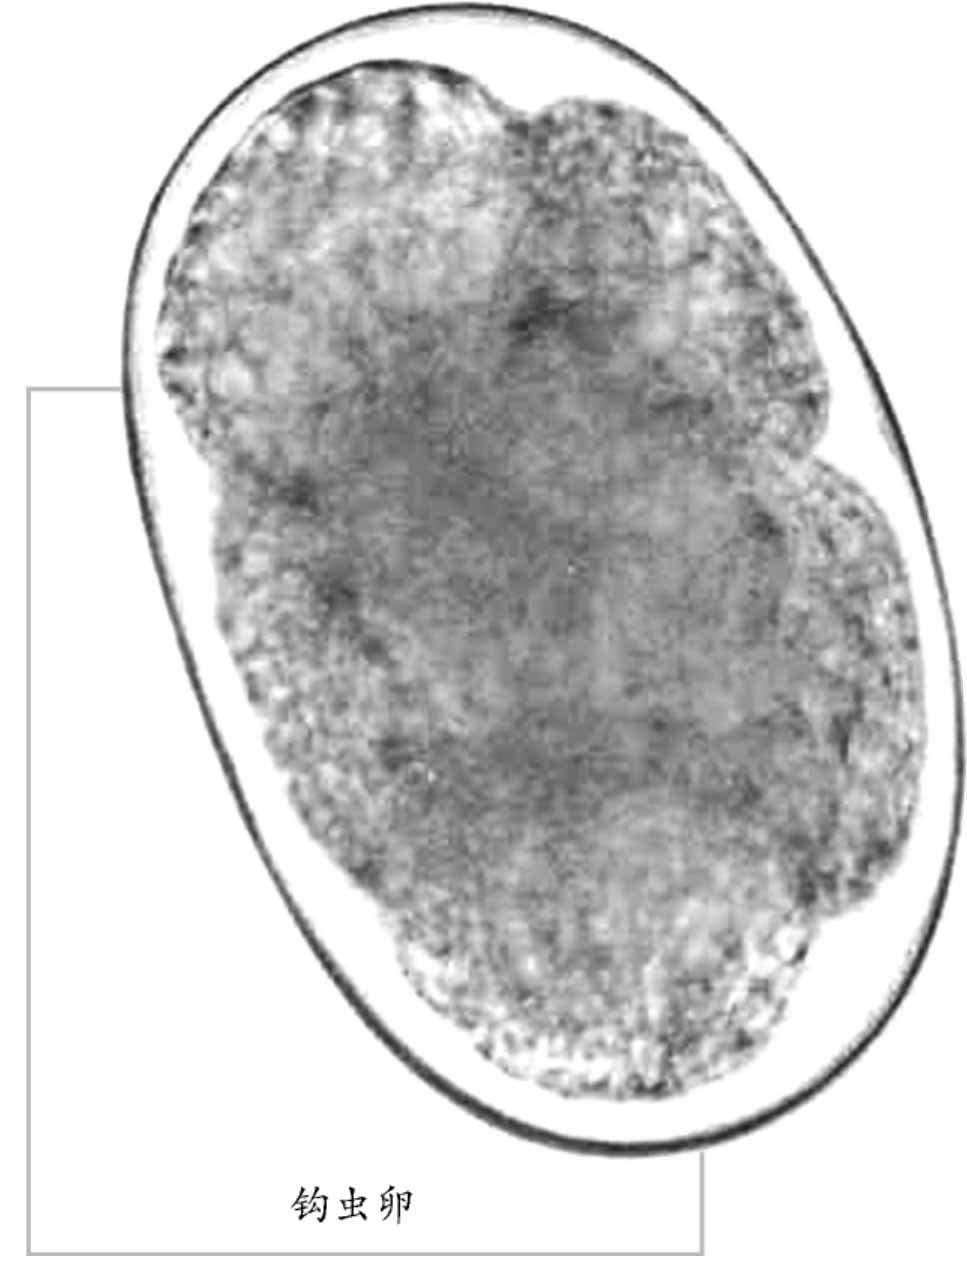

钩 虫

钩虫是钩口科线虫的统称,发达的口囊是其形态学的特征。在寄生人体消化道的线虫中,钩虫的危害性最严重,由于钩虫的寄生,可使人体长期慢性失血,从而导致患者出现贫血及与贫血相关的症状。钩虫呈世界性分布,尤其在热带及亚热带地区,人群感染较为普遍。据估计,目前,全世界钩虫感染人数达9亿左右。在我国,钩虫病仍是严重危害人民健康的寄生虫病之一。

寄生人体的钩虫,主要有十二指肠钩口线虫,简称十二指肠钩虫;美洲板口线虫简称美洲钩虫。另外,偶尔可寄生人体的锡兰钩口线虫,其危害性与前两种钩虫相似。犬钩口线虫和巴西钩口线虫的感染期蚴,虽也可侵入人体,引起皮肤幼虫移行症。因幼虫移行蜿蜒弯曲,引起皮疹呈匐行线状,故称匐形疹。但幼虫不能发育为成虫。

钩虫体长约1厘米,半透明,肉红色,死后呈灰白色。虫体前端较细,顶端有一发达的口囊,由坚韧的角质构成。因虫体前端向背面仰曲,口囊的上缘为腹面、下缘为背面。十二指肠钩虫的口囊呈扁卵圆形,其腹侧缘有钩齿2对,外齿一般较内齿略大,背侧中央有一半圆形深凹,两侧微呈突起。美洲钩虫口囊呈椭圆形。其腹侧缘有板齿1对,背侧缘则有1个呈圆锥状的尖齿。钩虫的咽管长度约为体长的1/6,其后端略膨大,咽管壁肌肉发达。肠管壁薄,由单层上皮细胞构成,内壁有微细绒毛,利于氧及营养物质的吸收和扩散。

钩虫对人体的危害主要是由于成虫的吸血活动,致使患者长期慢性失血,铁和蛋白质不断耗损而导致贫血。由于缺铁,血红蛋白的合成速度比细胞新生速度慢,则使红细胞体积变小、着色变浅,故而呈低色素小细胞型贫血。患者出现皮肤蜡黄、黏膜苍白、眩晕、乏力,严重者作轻微活动都会引起心慌气促。部分病人有面部及全身浮肿,尤以下肢为甚,以及胸腔积液、心包积液等贫血性心脏病的表现。肌肉松弛,反应迟钝,最后完全丧失劳动能力。